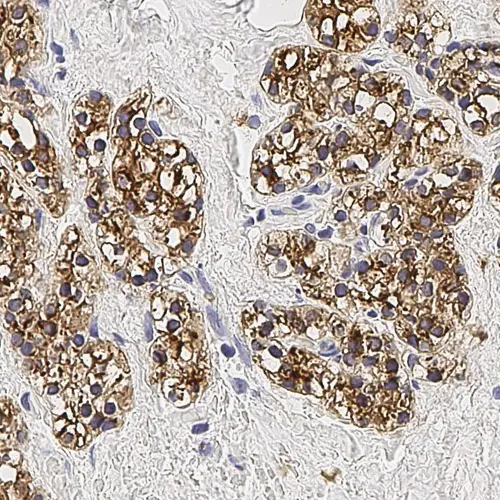

Human parathyroid adenoma: immunohistochemical staining for Parathyroid Hormone. Note membrane/cytoplasmic staining of tumor cells. Parathyroid Hormone: clone 105G7

Das Parathormon (PTH) ist der wichtigste Regulator des Calciumspiegels im Blut. Die Hauptzellen sind in der Nebenschilddrüse am stärksten verbreitet. Sie sind verantwortlich für die Sekretion des Parathormons. Antikörper gegen das Parathormon sind zusammen mit Antikörpern gegen Thyreoglobulin nützlich, um parathormonabgeleitete Läsionen von thyroidabgeleitete Läsionen zu differenzieren.